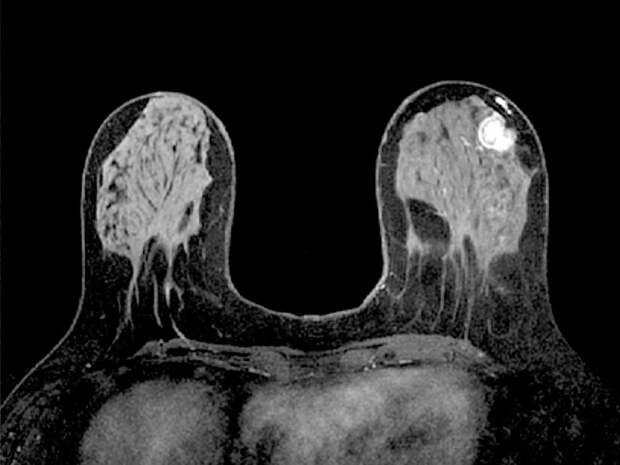

Для повышения информативности исследование почти всегда проводится с динамическим контрастным усилением. В вену пациентки вводится специальное парамагнитное контрастное вещество (на основе гадолиния). Здоровые и патологически измененные ткани (особенно злокачественные опухоли) накапливают контраст с разной скоростью и интенсивностью, что позволяет рентгенологу оценить характер кровоснабжения образований и сделать вывод об их природе.

Расшифровкой снимков занимается врач-рентгенолог, специализирующийся на патологии молочных желез. Оценка проводится по международной системе BI-RADS (Breast Imaging-Reporting and Data System).

- Морфология образования: Форма (овальная, округлая, неправильная), контуры (ровные, неровные, спикулообразные).

- Кинетика накопления контраста: Оценивается, как быстро и интенсивно образование накапливает контраст, а также как быстро он "вымывается". Злокачественные опухоли часто характеризуются быстрым и интенсивным накоплением с последующим быстрым "вымыванием" (кинетика типа III).